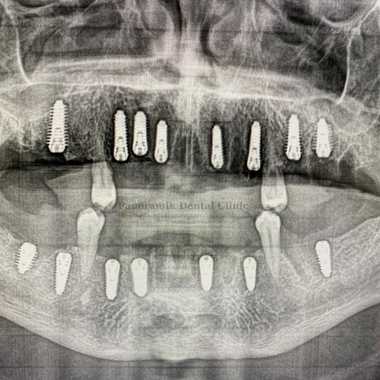

All on Eight Implants Technique

What Is All on 8 Implantation? How Is It Used?

All on 8 implants technique are used when a person is missing teeth. After implantation, a temporary denture is placed if necessary. The gums heal in about a week, and it takes three to six months of time for the bone to fully heal.

All on 8 implant is a dental procedure where eight implants are fixed in the tooth row, it is mainly used for people who have lost 80% of their teeth.

The all on 8 implant technique allows 28 teeth to be placed in the entire jaw. With this system, chewing comfort is improved because the load is distributed over the entire jaw. In addition, it is possible to segment the patient's teeth, which means that if a problem arises in the future, it will be easy to identify where it is located and treat it in a short period of time.